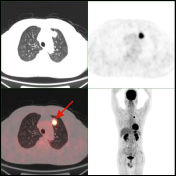

早期肺癌发现及鉴别:PET/CT显像示左肺上叶前段软组织灶(左图所示),糖代谢明显增高(SUVmax=15.3),经手术病理证实为肺腺癌。